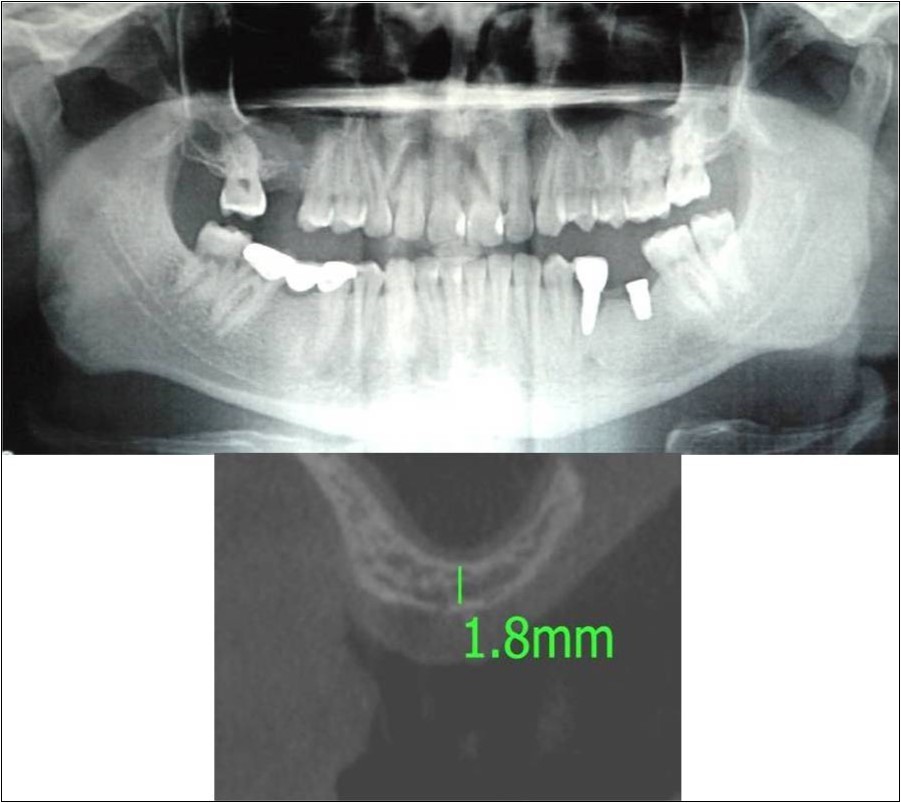

Case Report 6:

A 25 years old young male patient reported to the Department of Oral and Maxillofacial Surgery, D.A.P.M.R.V Dental College and Hospital seeking options for implant supported prosthesis for rehabilitation of missing right first molar. The tooth was extracted 6 months ago because of gross loss of tooth structure and poor prognosis for root canal treatment. Patient did not give history of any existing sinus pathologies. All possible rehabilitative options were explained to the patient and a treatment plan of replacement of missing tooth with implant supported prosthesis was finalized.

Clinical and Radiological Assessment:

1.Partially edentulous maxillary arch with missing 16;

2.Increased pneumatisation of right and left maxillary sinus;

3.Height of available bone- 1.8mm;

4.Transverse thickness of available bone (CBCT evaluation)- 6.2mm;

5.Implant supported prosthesis i.r.t 35 and 36;

6.Fixed partial denture i.r.t 45, 46, 47;

7.Inter-ridge space adequate to place implant (12mm).

Treatment:

Patient underwent the procedure of direct sinus elevation using sinus lateral approach kit. After crestal and vertical release incisions, muco-periosteal flap was raised to expose the buttress region. A bony window of 1cm diameter was created; sinus lining identified and elevated up to receive calcium phosphosilicate as graft material and closure was achieved under local anaesthesia and strict aseptic protocols. Implant placement was planned to be carried-out after a period of 6 months to allow for the consolidation for graft and naive bone formation. At the end of 6 months, a repeat CBCT scan was advised to evaluate the increase in bone height. (Figure 17a,b, pre-treatment; Figure 18a,b, post-treatment)

Figure 17.a,b. Pre-treatment OPG and cross section of CBCT showing residual alveolar bone height for Case No.6;

Figure 18.(a,b) Post-treatment OPG and cross section of CBCT showing residual alveolar bone height for Case No.6;